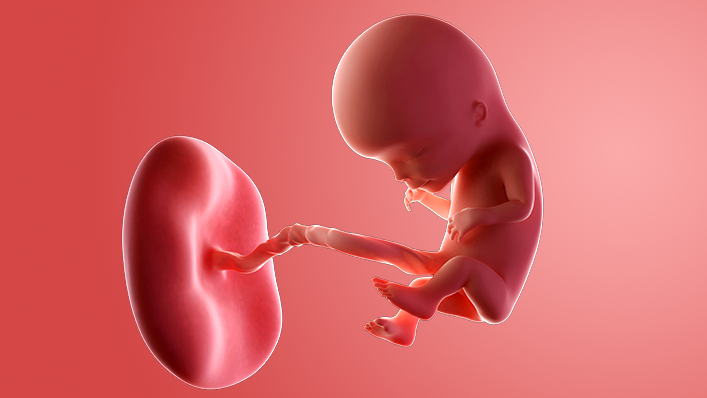

What does my baby look like?

Your baby, or foetus, is around 7.4cm long, which is about the size of a peach.

Your baby's ovaries or testes are fully developed inside and final tweaks are being made on the outside.

The baby is moving around. At first the movements are very jerky and random but then they start to look more deliberate. You may not feel any movement until around week 17.

Some babies suck their thumb in the womb. This actually serves a purpose as it helps to develop their sucking reflex. They'll need this when it comes to feeding.